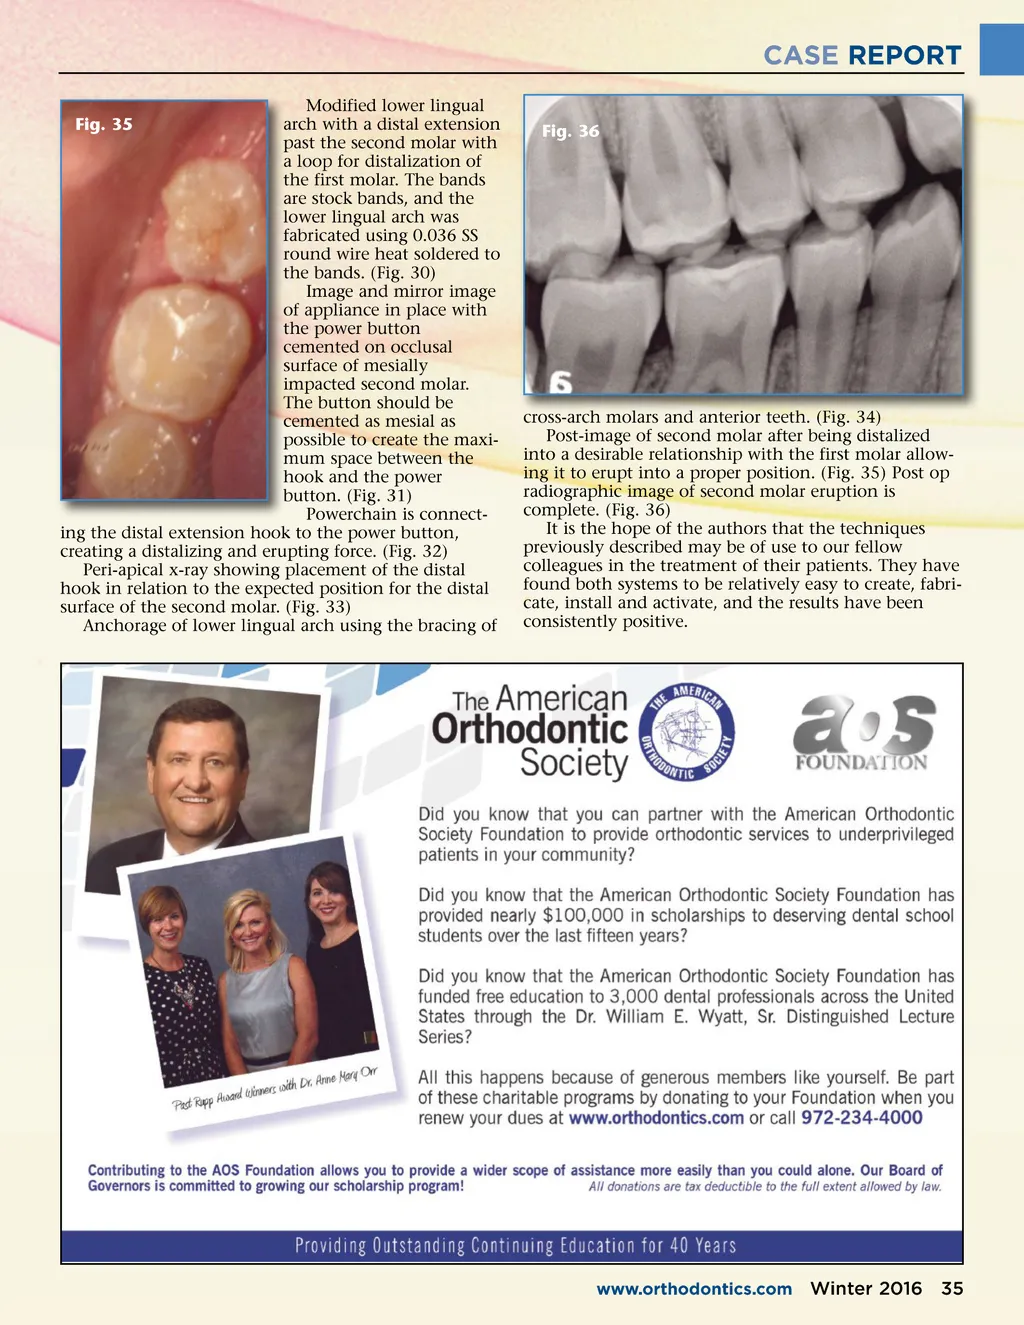

CASE REPORT Fig. 29 Fig. 32 Fig. 33 Fig. 30 Fig. 31 Case 3 Involving the Distalization of Impacted Second Permanent Molar Patient is a 15 year old female, intel-lectually delayed with multiple dental issues with partial cooperative behavioral issues who did not allow for a more conventional orthodontic approach. Partially impacted permanent second molar, visible clinical crown after Dr. EE had finalized a gingivectomy Fig. 34 uncovering part of the tooth to allow placement of an orthodontic power button.(Fig. 28) Radiographic image of mesial impaction of perma-nent second molar. (Fig. 29) 34 Winter 2016 JAOS